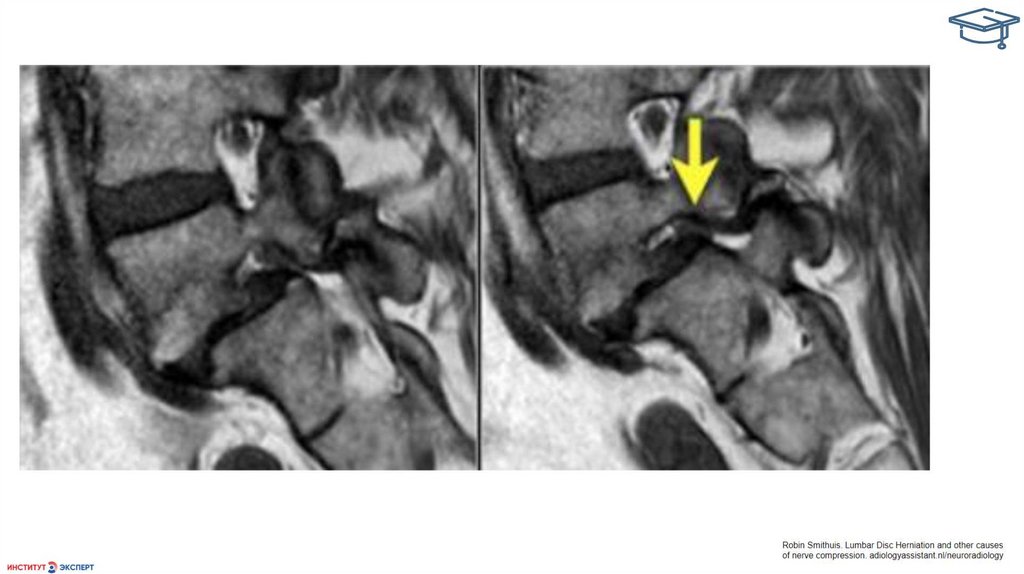

МРТ диагностика изменений межпозвонковых дисков